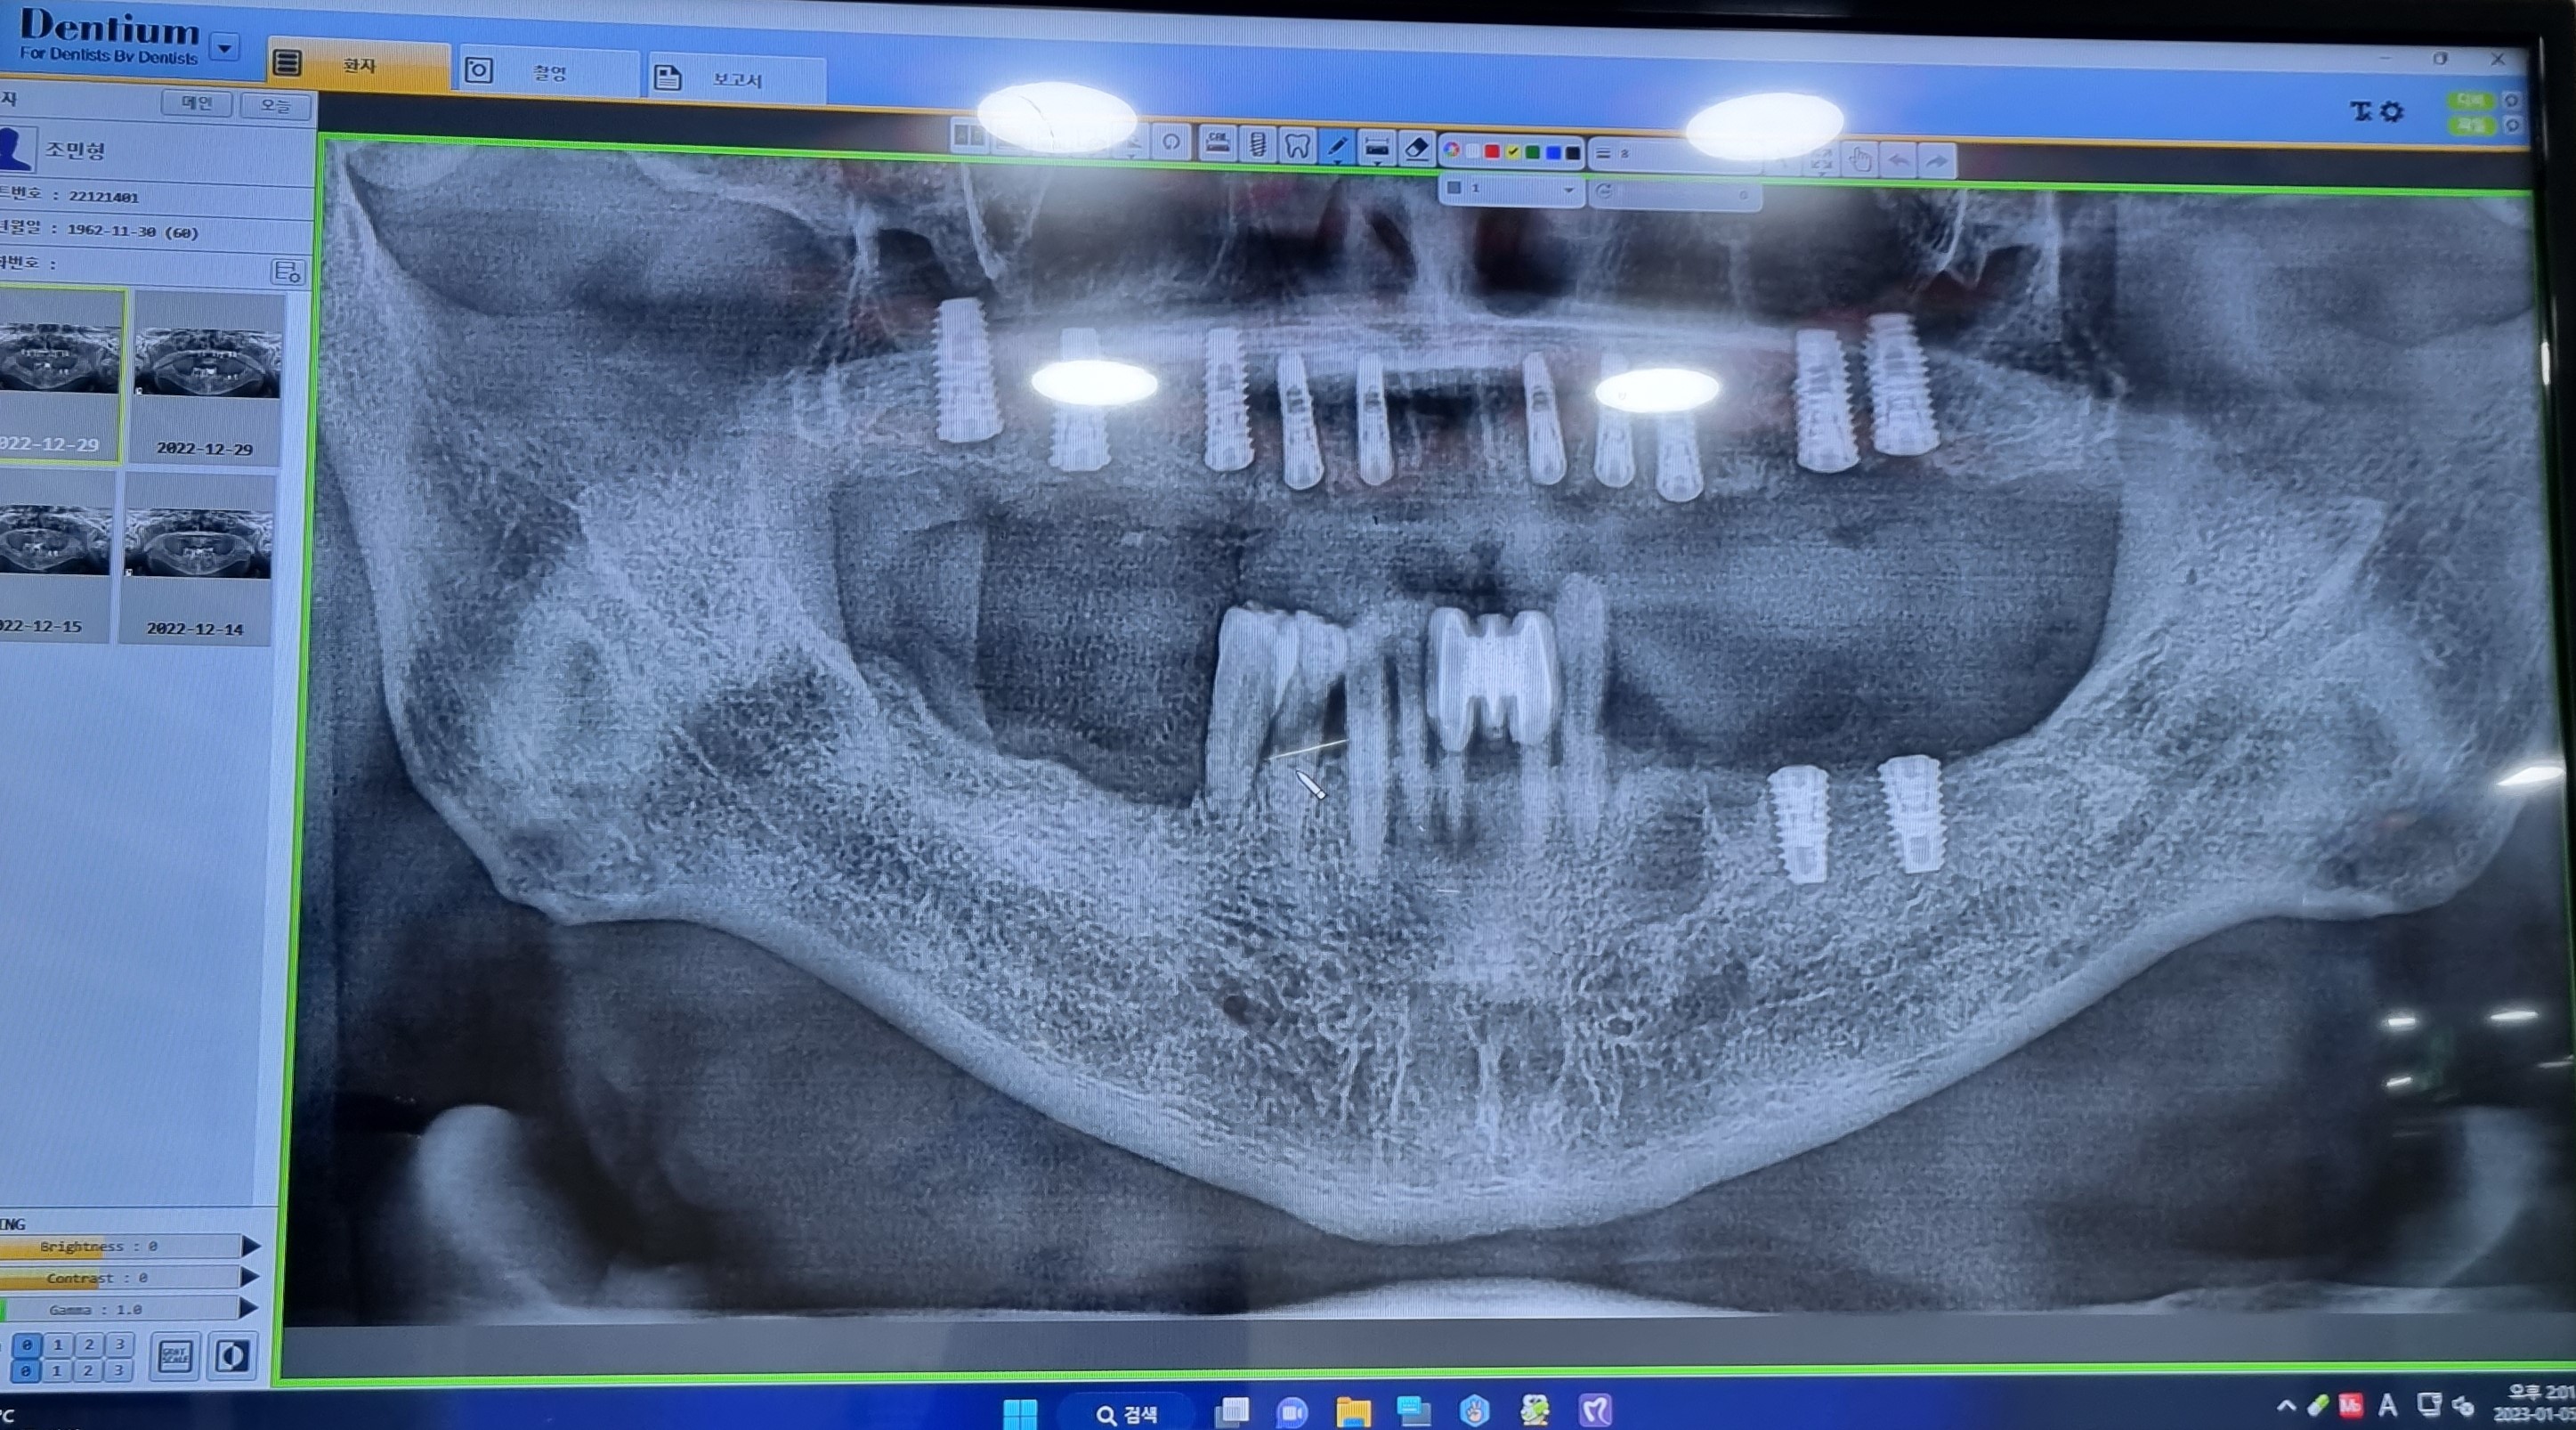

아랫니 하악下顎  2개를  발치拔齒후  36. 37 치조골이식술을  뼈속에  심는  과정으로  뼈이식과

임플란트dental implant  수술이  함께  진행하였습니다.

시술방법은 마취를 한 후 잇몸을 절개하여 턱뼈의 모양이 보이도록 벌려 준다.

임플란트dental implant 위치를 확인하고 드릴링drilling을 하여 턱뼈 안에 임플란트dental implant

들어갈 공간hole을  만들어 임플란트dental implant를 심는다.

수술시간 20분 치아를  빼고 1차 수술하면 앞니가 없는 체로 다녀야 하니  앞니 임플란트dental implant

임시치아는 언제  낄 수 있는지  걱정이  앞서는군요.

20221222

1차  윗니 상악上顎동 거상술

오늘   수술은  지난번  보다  어렵다고  합니다.

윗니 앞니 좌축 모두 7개  임플란트dental implant의  뿌리인  픽스쳐Fixture를  잇몸을  절개하여

잇몸뼈에  식립植粒하는날

상악上顎 13.12.22.23.24.26.27 뼈이식과 인공치근 식립植粒 함께  진행하였습니다.